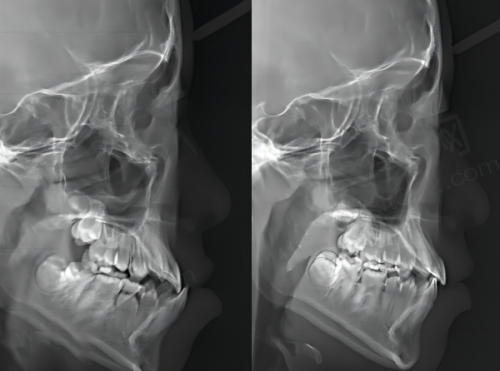

在种植技术方面,医院采用了CAD导航微创种牙技术。这种技术就像是给医生装了一个“导航系统”,能让医生更精细地植入种植体,减少手术创伤,缩短手术时间,患者术后修复也更快。而且,医院的穿颧种植技术可以解决无骨难题,让那些原本因为牙槽骨条件不好而无法种牙的患者也能拥有健康的牙齿。